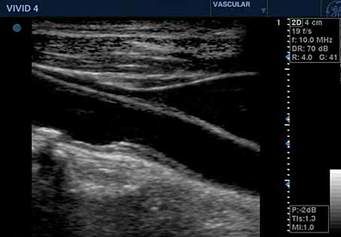

- Doppler-Sonographie der hirnversorgenden Blutgefäße